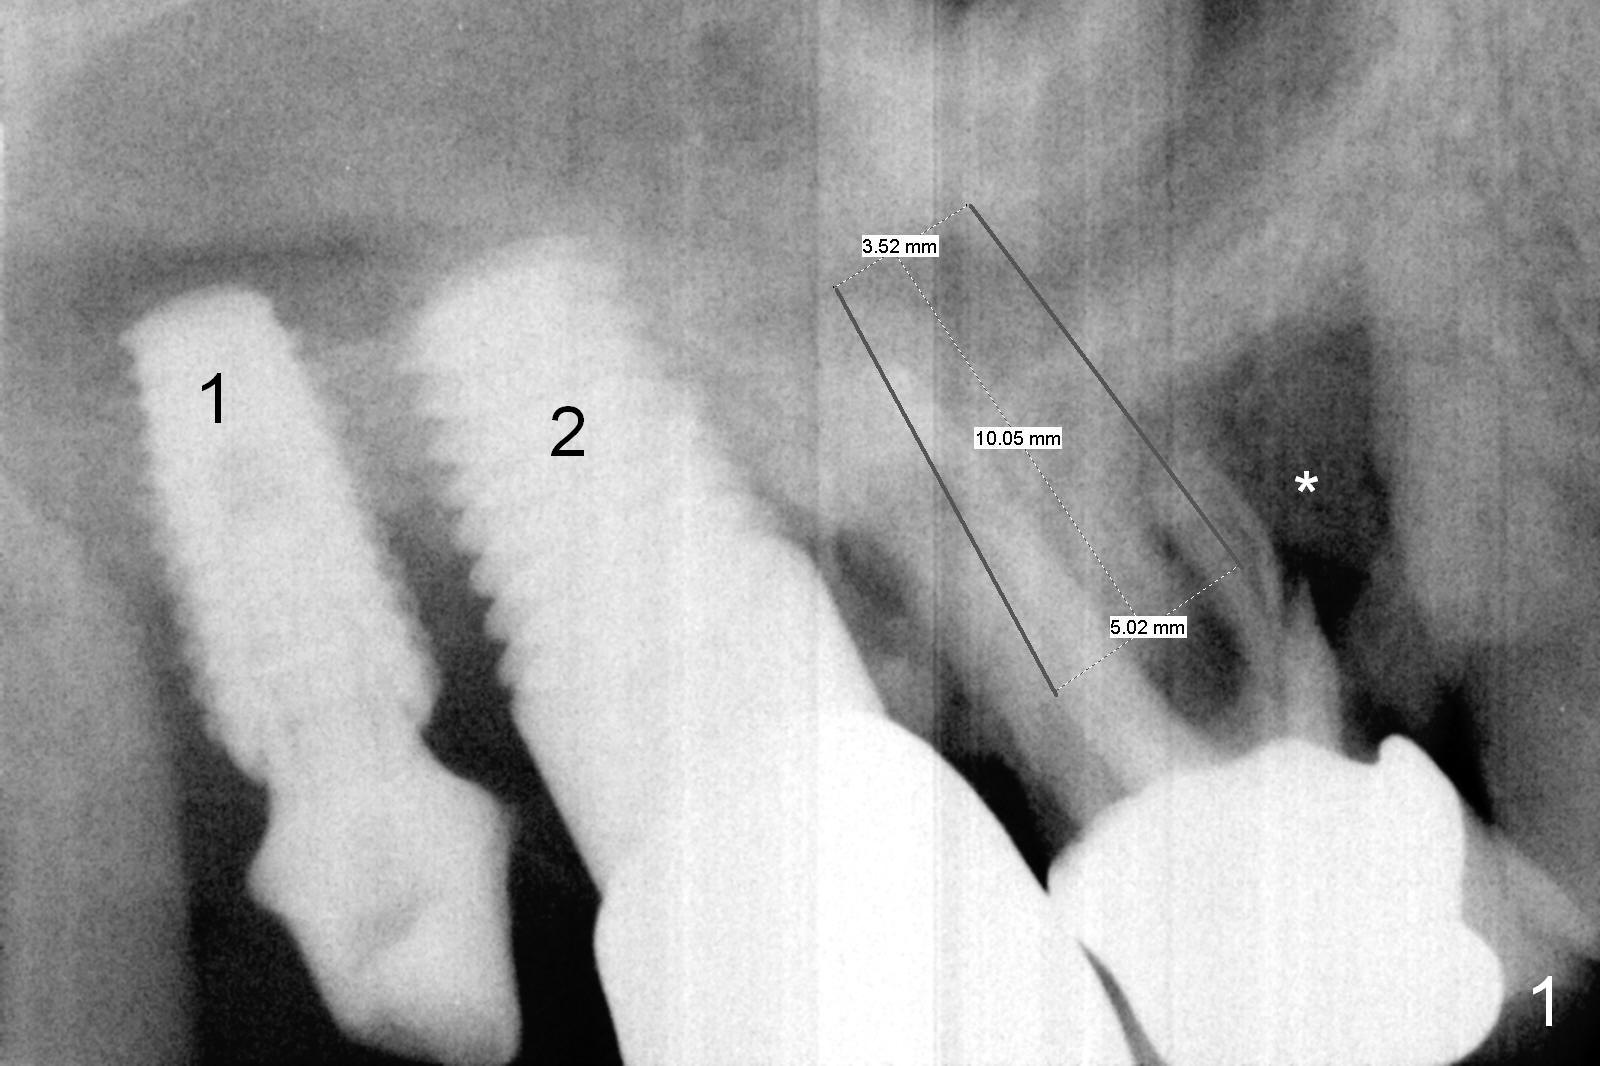

A 62-year-old man will return for #3 immediate implant, 2.5 years after #2 one and .5 year after #1 one (Fig.1). It appears that the available bone for the implant is the septum, which is not large. The implant is not expected to be large. Sinus lift is anticipated to obtain additional stability. Prepare osteotomes and bone expander kit. Since the bony defect is extensive (*), prepare more larger size of allograft than the small one and Osteogen. The amount of graft should be large, looking at the socket after extraction. The antibiotic will be Clindamycin. Use amalgam carrier for sinus lift and larger one for the rest of grafting. To keep the graft in place, try a large abutment, e.g., 7.5 mm. If there is severe gingival recession, draw blood for PRF. Take preop photos.